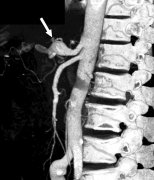

虽证实锁骨下近端狭窄/阻塞同时有椎动脉返流的病人通常无症状。 除少数病例外,通常近...